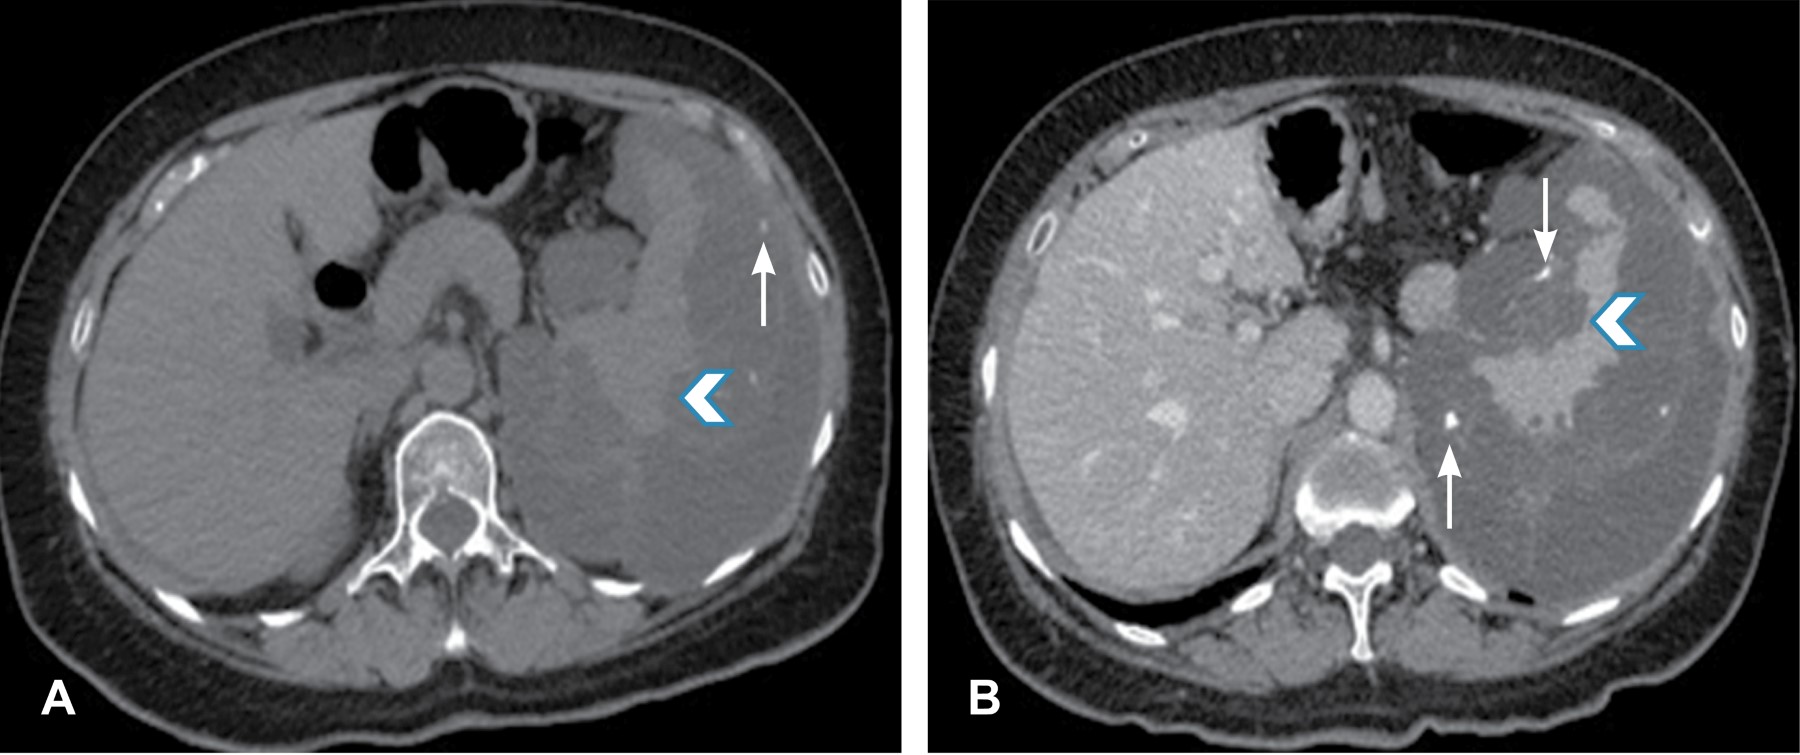

Se le solicitó una tomografía computarizada de abdomen en fase simple y contrastada; se encontró una lesión ovoidea, heterogénea a expensas de zonas hipodensas que alternaban con otras de mayor densidad, mostrando atenuación grasa dependiente del peritoneo que infiltraba y causaba festoneado del bazo, la lesión midió 29.1 × 14.2 × 27.3 cm (Figura 1). Tras la aplicación del medio de contraste se mostró reforzamiento heterogéneo con dilatación y tortuosidad de los vasos, esta masa causaba desplazamiento medial, caudal y ventral del riñón izquierdo, lateral y anterior del páncreas así como lateral del duodeno (Figura 2). Se realizó el diagnóstico de pseudomixoma peritoneal por tomografía. La paciente fue trasladada a un hospital de tercer nivel para su manejo.

Figura 2